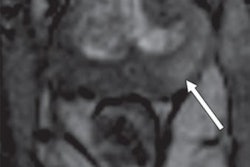

RSI-MRI corrects for magnetic field distortions found in other imaging techniques and focuses on water diffusion within tumor cells that exhibit a high nuclear volume fraction. This enables RSI to more accurately plot a tumor's location and allows for differentiation between tumor grades.

Senior author Dr. David Karow, PhD, an assistant professor of radiology at UCSD School of Medicine, said RSI allows clinicians to predict the grade of a tumor sometimes without a biopsy of the prostate tissue, while adding only 2.5 to five minutes to a pelvic MR scan in the study.

MRI (left) shows the prostate enhanced with RSI. The higher-grade tumor is indicated in orange and yellow. The image on the right shows a digitized section of the prostate with the tumors outlined with dotted lines. Images courtesy of Clinical Cancer Research.Greater accuracy helps customize treatment for each patient by identifying more aggressive cancers, which require immediate attention. The findings also suggest that RSI-MRI could eventually serve as a standalone, noncontrast screening tool that would take 15 minutes, compared with 40 to 60 minutes for a contrast-enhanced MRI scan.